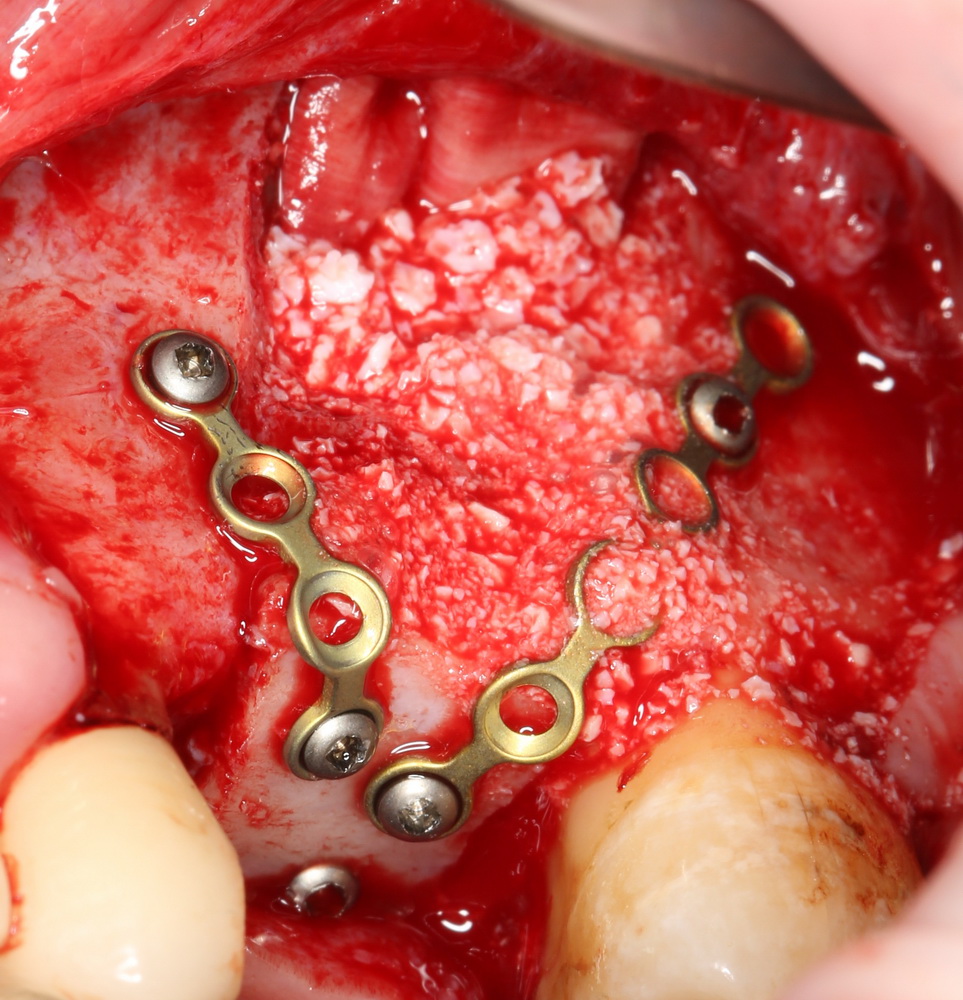

Итого, наиболее оптимальным в данной ситуации оказалась направленная тканевая регенерация с использованием барьерных мембран. В качестве барьерной мембраны у нас будет Geistlich BioGide. Ее очень легко адаптировать и позиционировать:

А в качестве трансплантата — аутокостная стружка, которую я насобирал заранее из области угла нижней челюсти:

Начну с того, что BioGide — это лучшее, что есть сейчас на рынке, а остальные мембраны ей завидуют. Как и в случае с макродизайном имплантов, именно физические свойства определяют как удобство использования, так и возможность достижения нужного результата. Прочность, эластичность, легкая адаптация и адгезия делают ненужными использование фиксирующих пинов. Мы просто закрываем мембраной графт — и все, можно накладывать швы:

В другом ракурсе видно, какой объем тканей мы восстанавливаем: